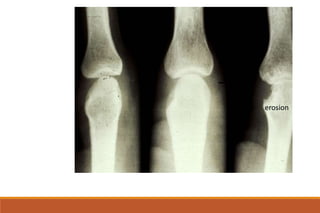

RHEUMATOID ARTHRITIS

X-rays

◦ The earliest changes occur in the wrist or feet and consist of soft

tissue swelling and juxta-articular demineralization.

◦ Later, diagnostic changes consisting of joint space narrowing and

erosions develop. The erosions are first seen at the ulnar styloid

and at the juxta-articular margin, where the bony surface is not

protected by cartilage.

◦ Diagnostic changes also occur in the cervical spine with C1-2

subluxation, but this can take several years to develop.